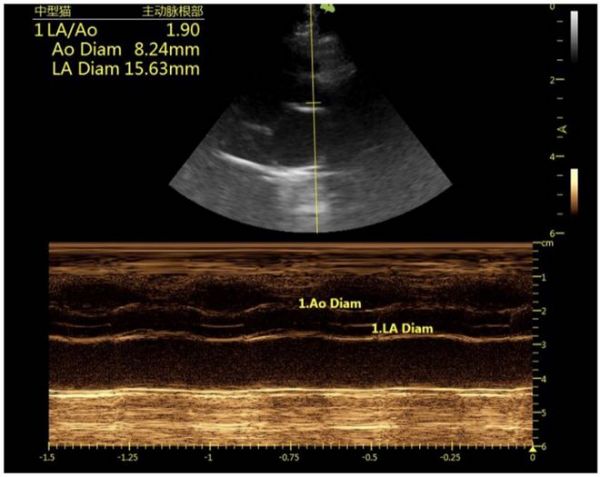

9. 进一步诊断结果

图4:右侧长轴四腔心 图5:右侧长轴四腔心

图6:右侧长轴五腔心

9.1 心脏超声结果分析

心超M-mode可见左心室舒张末期室中隔厚度约6.8mm,左室壁厚度约:7.8mm,均超过6 mm,提示肥厚性心肌病;左心房与主动脉内径比值约1.9(正常<1.5),提示左心房扩张,左心前负荷升高,有比较高的肺水肿风险。另外房间隔处存在左向右分流,存在房间隔缺损的情况,同时在心脏周围可见少量游离液性暗区,提示存在胸腔积液。